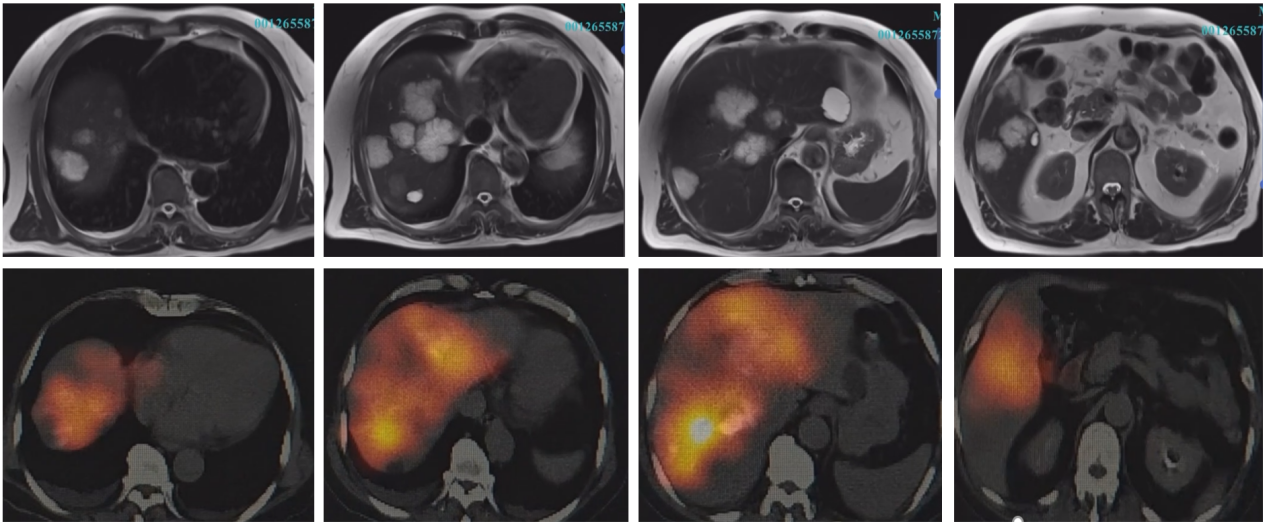

【本站讯】近日,绿帽社 普通外科肝胆外科在核医学科、放射科等科室支持下,顺利完成了1例复杂直肠癌肝多发转移瘤患者的钇90微球输注,术后SPECT/CT证实钇90微球均匀分布并较好覆盖转移病灶。该治疗方案由普通外科主任张宗利教授、普通外科常务副主任李涛教授等专家精心策划,普通外科肝胆外科刘炎锋副教授等具体实施。

肝多发转移瘤患者术前MRI提示肝内多发转移病灶,术后SPECT/CT证实钇90微球较好覆盖转移病灶